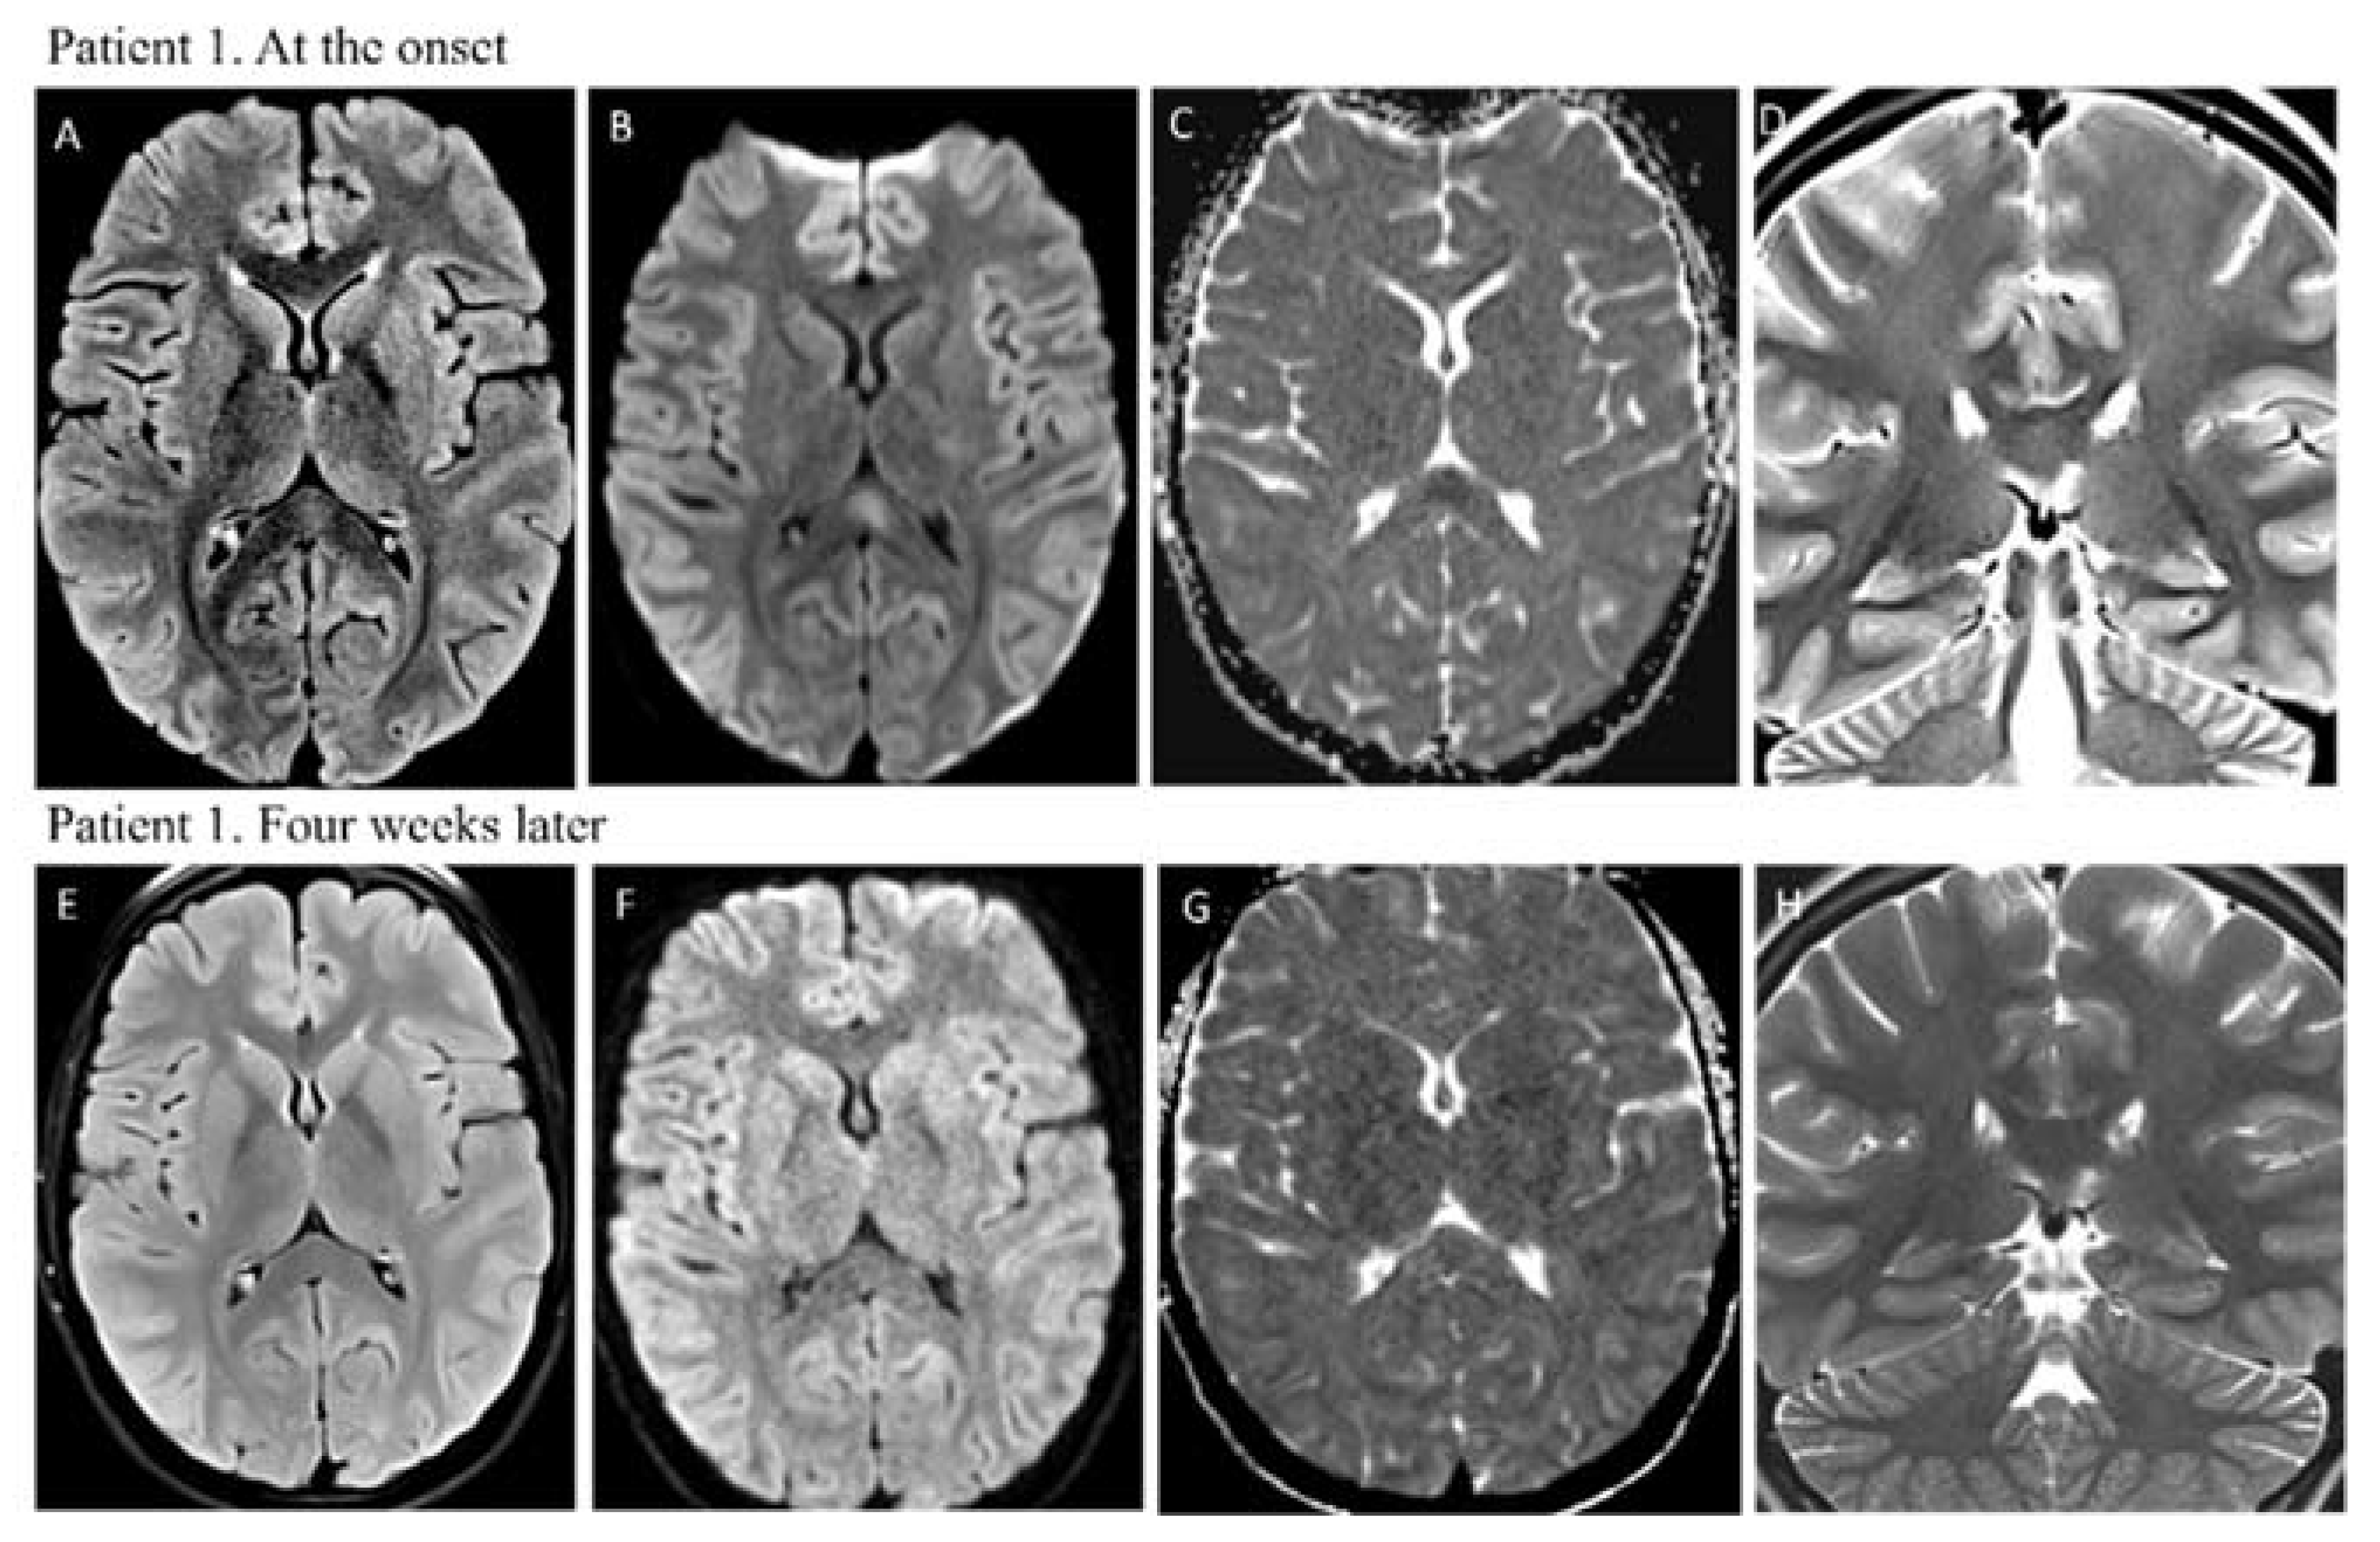

| Brain Imaging | MRI: hyperintensity on T2-weighted images in the splenium of the corpus callosum with restricted diffusion | MRI: hyperintensity on T2-weighted images in the splenium of corpus callosum with restricted diffusion |